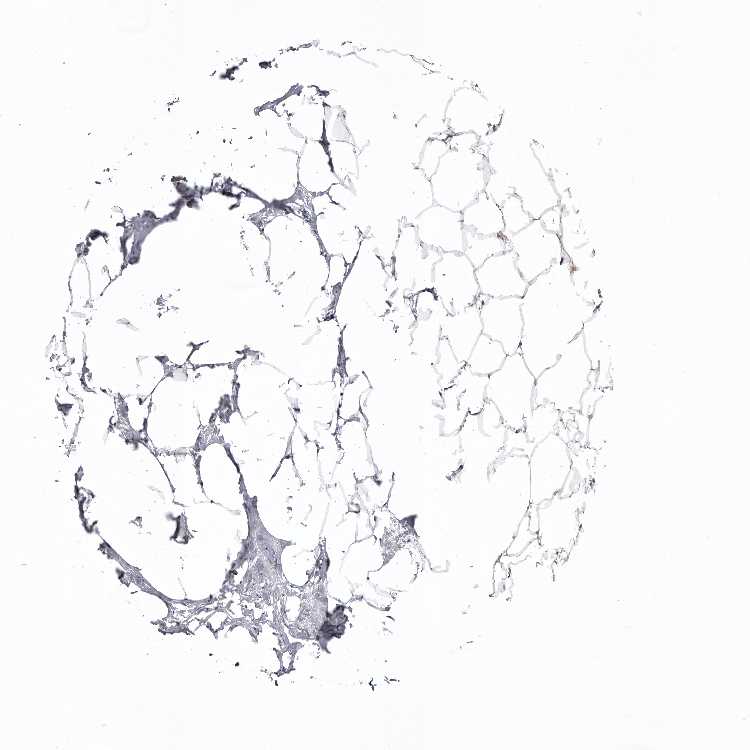

BREAST - HPA RNA-seqi

The RNA-seq details section shows detailed information about the individual samples used for the transcript profiling and results of the RNA-seq analysis.

Information about each individual sample is listed below, including gender, age, a tissue section image and estimated fractions of cell types. nTPM (normalized transcripts per million) values give a quantification of the gene abundance which is comparable between different genes and samples.

Female, age 52

Breast sample 373

nTPM: 138

Cell types%

Glandular cells:

15

Adipocytes:

5

Other cell types:

80